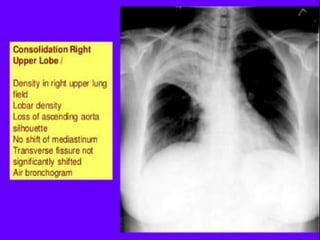

The key-findings on the chest X-ray are:

1-ill-defined homogeneous opacity obscuring vessels

2-Silhouette sign: loss of lung/soft tissue interface

3-Air-bronchogram

4-Extention to the pleura or fissure, but not crossing it

5-No volume loss

Chest radiograph The primaryrole of the chest radiograph is to differentiate pneumonia from other conditions that produce opacities (e.g. atelectasis, pleural effusion, pulmonary embolus, pulmonary contusion, mass lesions). The chest radiograph is also helpful in : following the progress of pneumonia, evaluating the response to therapy, and detecting complications (e.g., pleural effusion, empyema, congestive heart failure). 42

The key-findings onthe chest X-ray are: 1-ill-defined homogeneous opacity obscuring vessels 2-Silhouette sign: loss of lung/soft tissue interface 3-Air-bronchogram 4-Extention to the pleura or fissure, but not crossing it 5-No volume loss 43